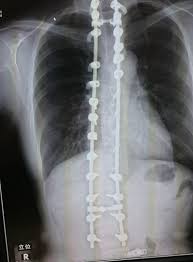

側 弯症側 手術側 ブログ側 ☆延長手術・・・☆側 -側 側わん症:VEPTRの会側 手術が必要な側弯症側 |側 ブログ側 |側 東京都品川の整体なら東京脊柱専門整体院側 側弯症対策!手術を避けるために日常で気をつけること側 |側 大阪市西淀川区佃の整体「なかむら鍼灸接骨院」千船駅徒歩4分側 側弯症コルセット側 術後側 手術が必要な側弯症5選側 -